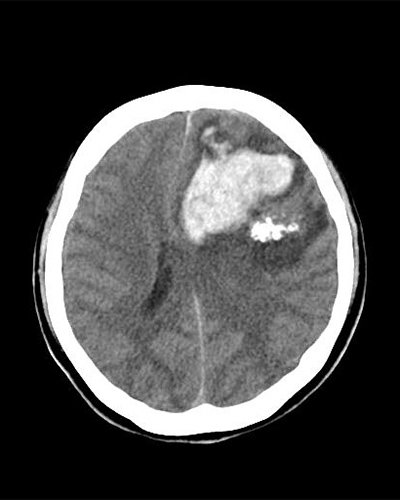

- 脳動静脈奇形

脳動静脈奇形(AVM)の脳外科治療には主に3つの方法があります。1)開頭手術による外科的摘出、2)血管内治療(カテーテルを用いた塞栓術)、3)定位放射線治療(ガンマナイフなど)です。AVMの大きさや部位、患者の状態によってこれらの治療を単独もしくは組み合わせて行います。

左前頭葉AVM

術前

術後